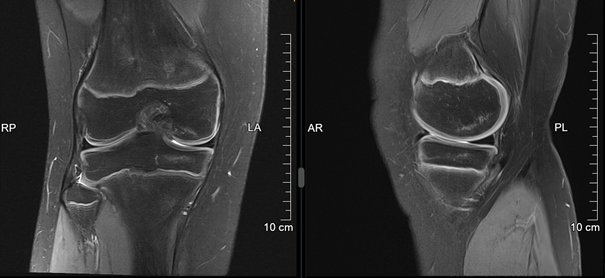

Osteochondritis dissecans

Die Ursache der Osteochondritis dissecans ist multifaktoriell und der Pathomechanismus noch nicht gänzlich geklärt. Das repetitive Trauma spielt eine wesentliche Rolle, häufig sind sportlich aktive Kinder und Jugendliche betroffen. Hormonelle, vaskuläre oder Erbfaktoren können als mögliche Ursache eine Rolle spielen. Die Schmerzen sind belastungsabhängig, im Spätstadium kann es zu Blockaden kommen. Das MRI ist die beste Untersuchung, um das Stadium zu beurteilen und somit das therapeutische Vorgehen zu entscheiden. Meistens handelt es sich zunächst um eine konservative Therapie mit Schonungsmassnahmen und Sportkarenz von 6 Wochen bis 3 Monate. Diese Entscheidungen müssen individuell erfolgen. Zu den operativen Therapien in schweren Stadien gehören die retrograde (knorpelschonende) Anbohrung, arthroskopische- oder offene Refixation. Ist dies nicht möglich, kann bei kleinen freien Gelenkskörpern die Entfernung ausreichen. Bei grösseren Defekten kommen Rekonstruktionen infrage. Grundsätzlich gilt, dass die Prognose bei jüngeren Patienten mit offenen Wachstumsfugen besser ist als nach Fugenschluss.